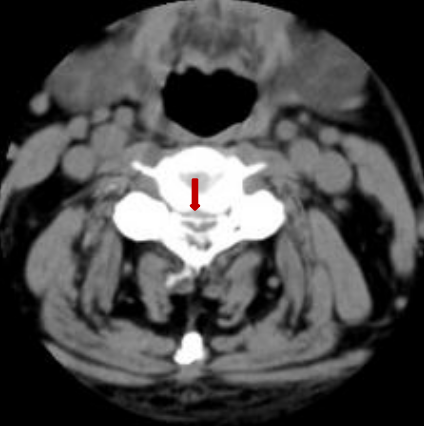

颈后路术后颈椎CT。

后入路术后见颈部椎管后方减压范围满意,骨性结构破坏小。

颈前路术后颈椎CT

前入路术后见颈椎间盘突出组织摘除完全。闫先生经住院治疗15天出院,治疗效果非常满意。